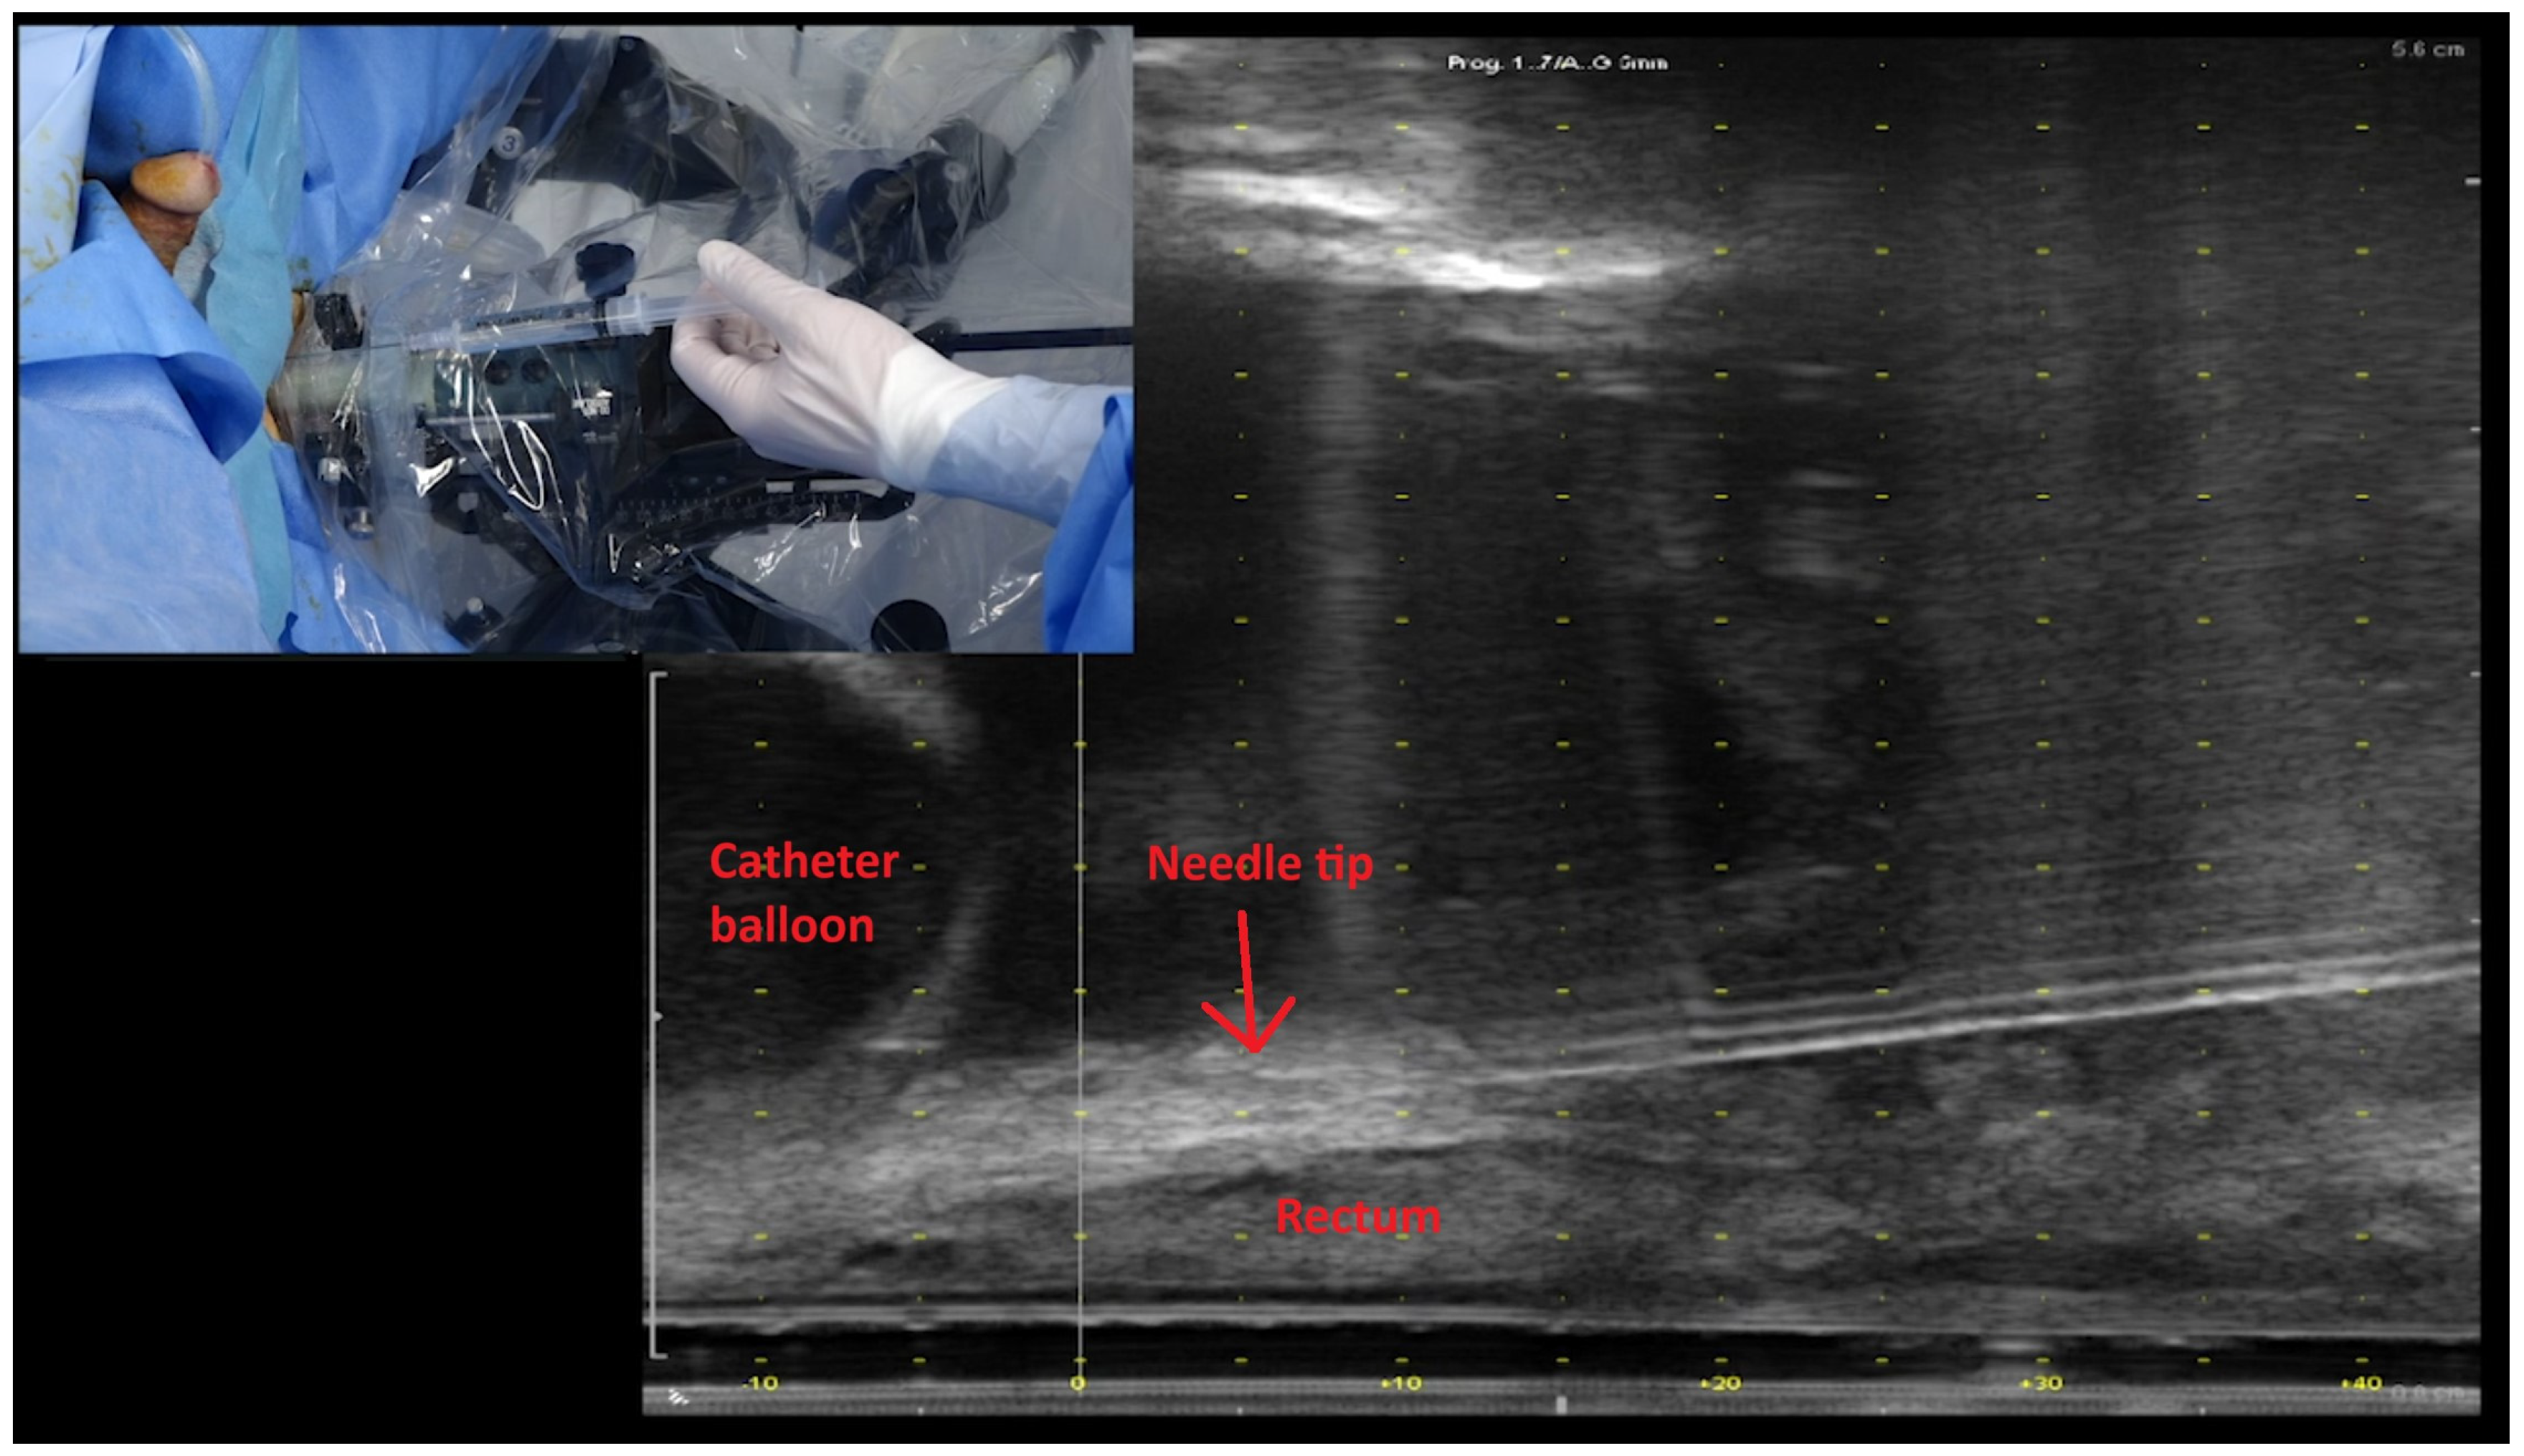

Patients underwent rectal spacing with either hyaluronic acid (Barrigel®, Palette Life Sciences, Santa Barbara, CA, USA) or hydrogel (SpaceOAR®, Boston Scientific, Massachusetts, Marlborough, MA, USA). The insertion technique is demonstrated in Figure 1. The rectal spacer was inserted into the perirectal fat posterior to the retained Denonvillier’s fascia between the bladder and anterior rectal wall using a transperineal approach under TRUS guidance. An indwelling urinary catheter was inserted to help delineate the vesico-urethral anastomosis (VUA). The perirectal fat was identified between the bladder and anterior rectum. An 18G spinal needle (Quincke Type Point® Spinal Needle, BD, Stockholm, Sweden) was inserted using a freehand technique targeting the midline of the prostate bed under sagittal TRUS guidance. Hydrodissection of the perirectal fat in the sagittal midline with 3 to 5 mL of sterile saline was attempted and, if successful, followed by insertion of 6 to 9 mL of hyaluronic acid (66% of cases) or hydrogel. After insertion, the vesico-rectal separation was calculated by measurement at the midline of spacer’s sagittal length. Pre- and post-spacer insertion images can be seen in Figure 2.

Figure 1.

Ultrasound image demonstrating the insertion of needle to the level of the vesico-ureteric anastomosis and just prior to hydrodissection and its relationship to the rectum and bladder neck (as outlined by the catheter balloon). Inset: transperineal approach for insertion of rectal spacer; here, the syringe contains normal saline ready for hydrodissection.